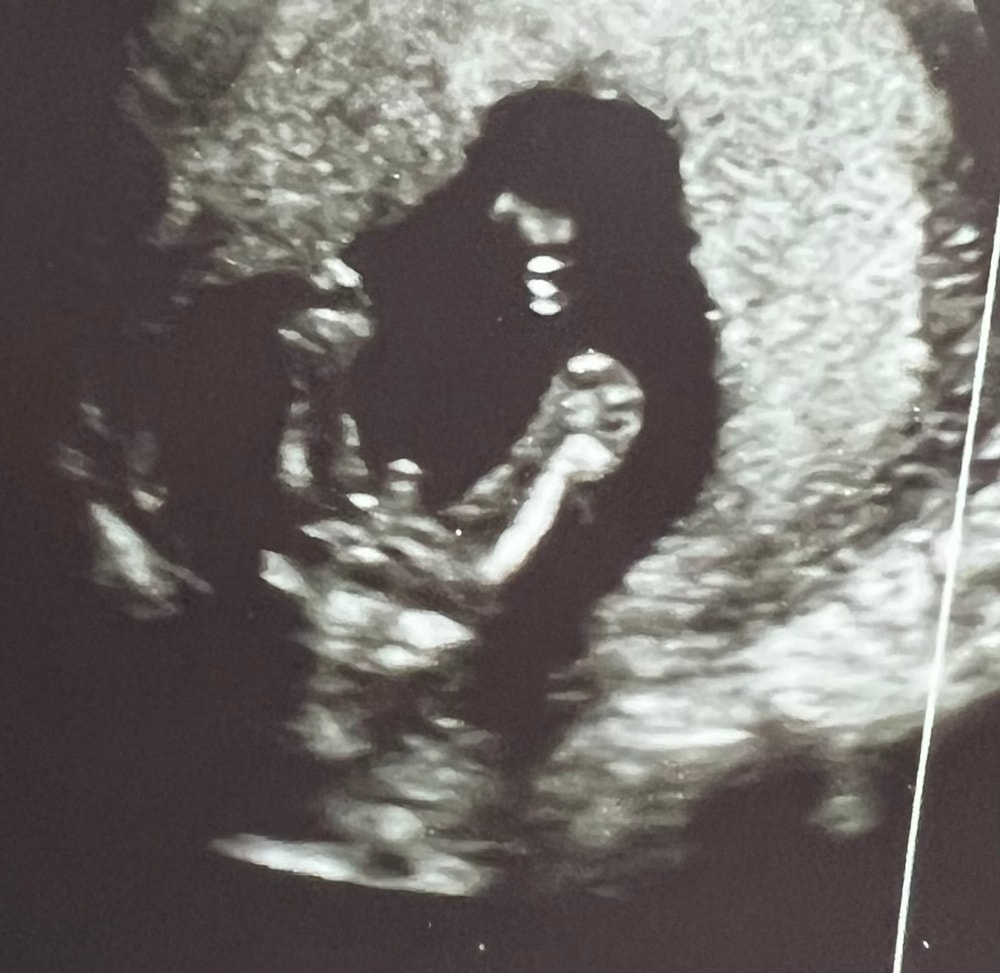

Мальчик в 16 недель Ракурс снизу вверх между ножек Изображение

29.10.2025